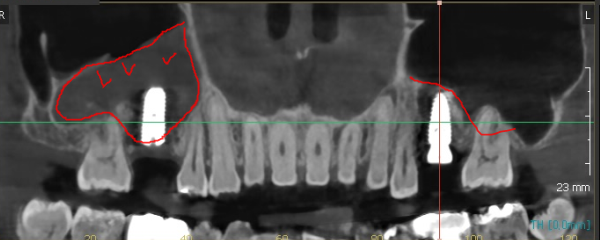

240320 치료를 해도 재발이 잘되는 상악동염 ㅠㅠ